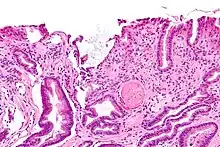

GAVE is characterized by dilated capillaries in the lamina propria with fibrin thrombi. The main histomorphologic differential diagnosis is portal hypertension, which is often apparent from clinical findings.